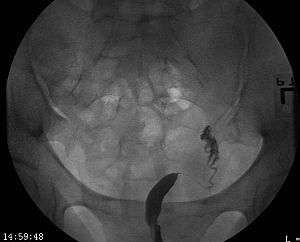

A unicornuate uterus as seen on a hysterosalpingogram

A unicornuate uterus represents a uterine malformation where the uterus is formed from one only of the paired Müllerian ducts while the other Müllerian duct does not develop or only in a rudimentary fashion. The sometimes called hemi-uterus has a single horn linked to the ipsilateral fallopian tube that faces its ovary.